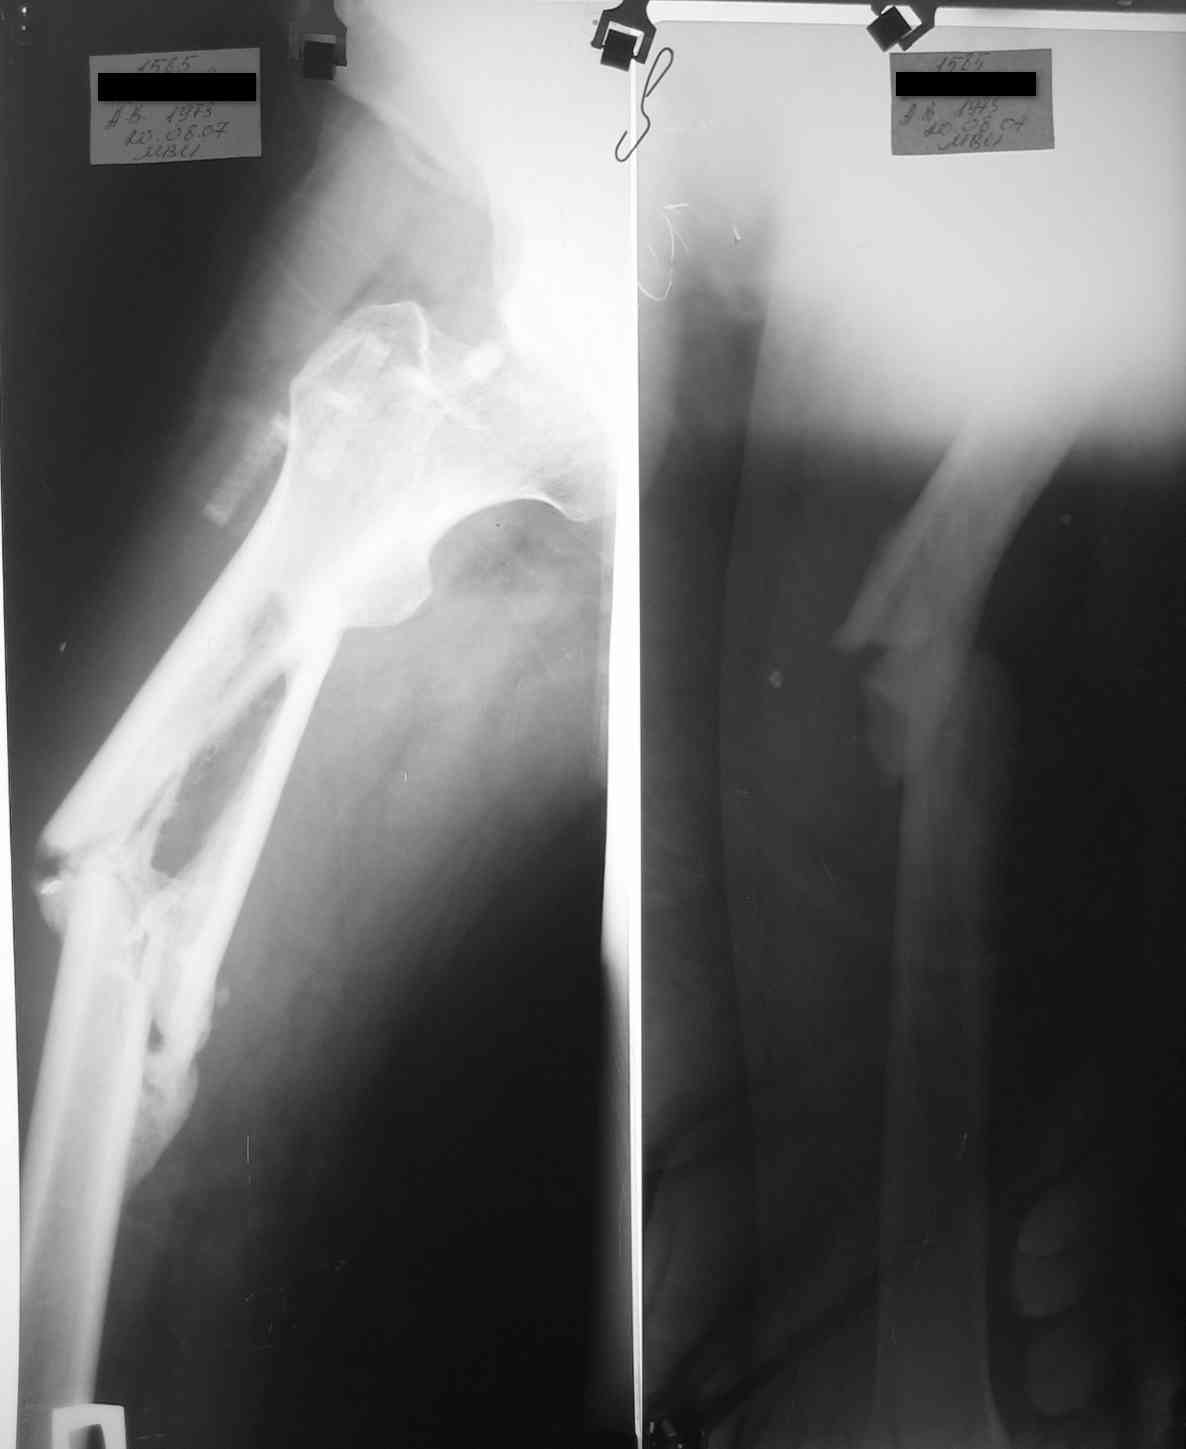

уважаемые коллеги, поступил пациент, через 6 месяцев после травмы, который лечился 3 месяца

на скелетном вытяжении, затем гипс еще 1,5 месяца, дозированная нагрузка через 3,5 месяца

после травмы. Дней 5 назад поскользнулся в ванной, почувствовал боль в бедре, появилась

деформация. Оперирован у нас, произведен остеосинтез блокирующим стержнем ,перелом не

открывался, был "доломан" на столе. меня интересует вариант вальгирования гвоздя в этом

случае. И по-вашему какие ерспективы у этого клиента?